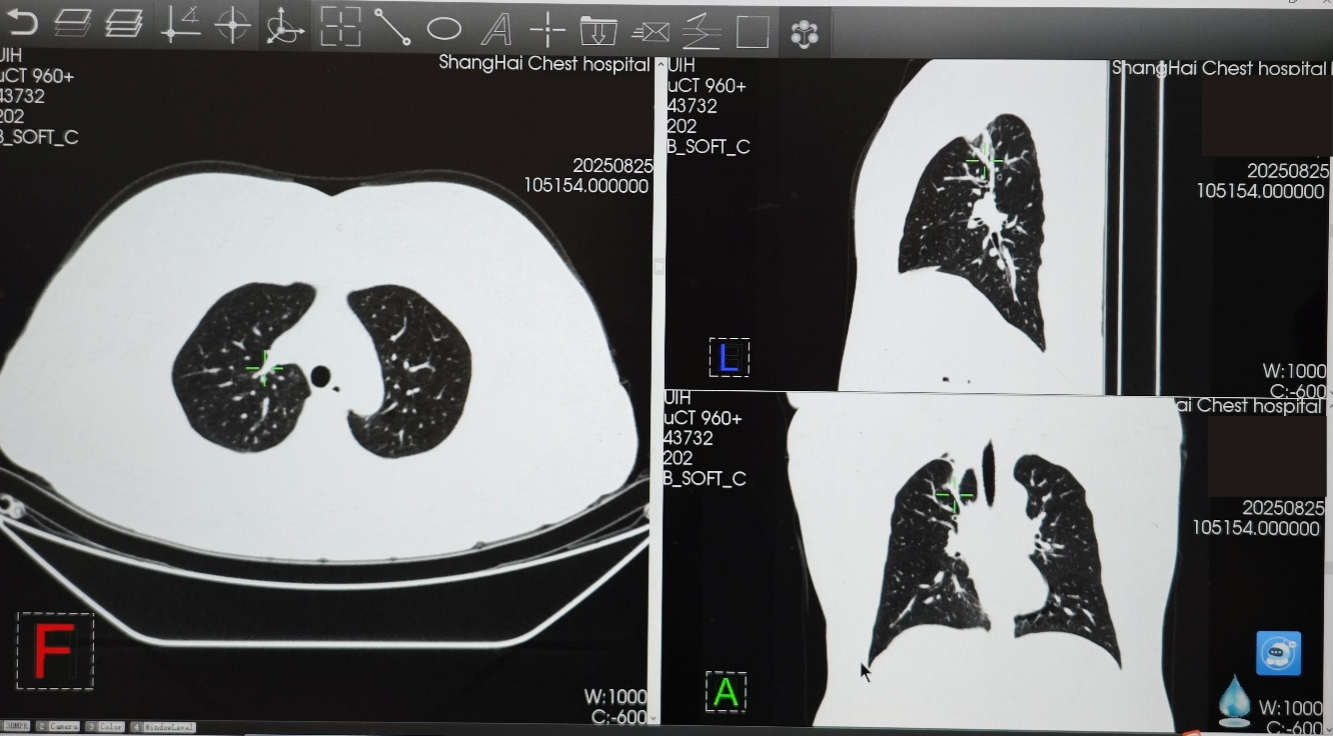

在变更骨保护药物方案前,患者免疫联合治疗达到并维持SD状态约10个月,在使用培美曲塞+PD-1+抗血管药物+地舒单抗后,患者肿瘤再次开始缩小,2025年2月复查胸部CT时,右肺上叶病灶缩小至24×11mm,达到PR。2025年8月复查胸部CT时,右肺上叶病灶进一步缩小至22×6mm,最佳疗效PR

2025.01-2025.08:免疫治疗联合地舒单抗后,肺部原发灶在长期SD后进一步缩小达到PR,地舒单抗可能突破了骨转移导致的免疫抑制,联合免疫治疗,助力实现逆转抑制、协同增效的全身获益。